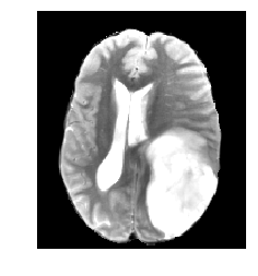

Medical image segmentation methods normally perform poorly when there is a domain shift between training and testing data. Unsupervised Domain Adaptation (UDA) addresses the domain shift problem by training the model using both labeled data from the source domain and unlabeled data from the target domain. Source-Free UDA (SFUDA) was recently proposed for UDA without requiring the source data during the adaptation, due to data privacy or data transmission issues, which normally adapts the pre-trained deep model in the testing stage. However, in real clinical scenarios of medical image segmentation, the trained model is normally frozen in the testing stage. In this paper, we propose Fourier Visual Prompting (FVP) for SFUDA of medical image segmentation. Inspired by prompting learning in natural language processing, FVP steers the frozen pre-trained model to perform well in the target domain by adding a visual prompt to the input target data. In FVP, the visual prompt is parameterized using only a small amount of low-frequency learnable parameters in the input frequency space, and is learned by minimizing the segmentation loss between the predicted segmentation of the prompted target image and reliable pseudo segmentation label of the target image under the frozen model. To our knowledge, FVP is the first work to apply visual prompts to SFUDA for medical image segmentation. The proposed FVP is validated using three public datasets, and experiments demonstrate that FVP yields better segmentation results, compared with various existing methods.